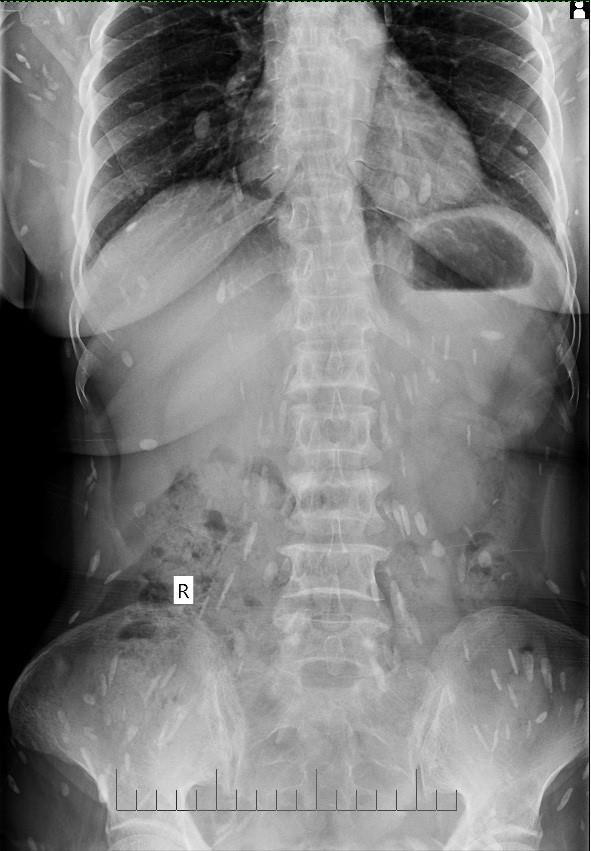

Ngày 19/3 gia đình đưa bà đến bệnh viện để khám. Qua thăm khám, xét nghiệm, siêu âm, chụp X-quang, các bác sĩ kết luận bệnh nhân bị mắc bệnh sán lá gan sinh sống trong cơ thể đã nhiều năm, đang sinh sôi, lan ra trong nhiều bộ phận cơ thể. Người bệnh được kê thuốc và hướng dẫn lên bệnh viện tuyến trên để theo dõi, điều trị tiếp.